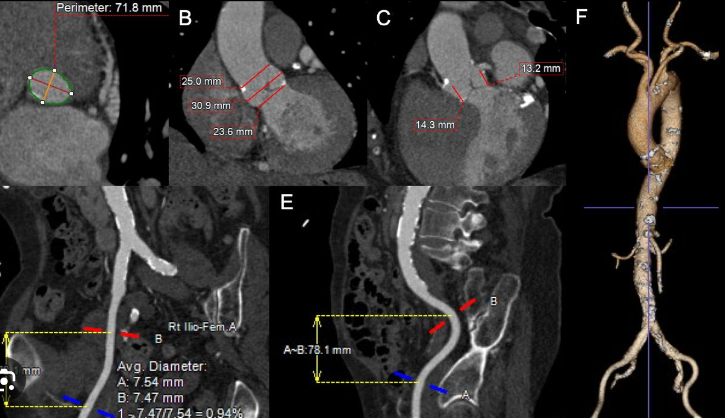

Διεξάγεται σε αξονικό τομογράφο πολλαπλών τομών (>128 detectors) με εξειδικευμένο λογισμικό απεικόνισης και επεξεργασίας των δεδομένων της παλλόμενης καρδιάς. Με την χρήση ακτίνων Χ, υπό ηλεκτροκαρδιογραφικό συντονισμό, διεξάγεται λήψη εγκάρσιων τομών της καρδιάς και με ειδική επεξεργασία δημιουργείται τρισδιάστατη εικόνα του καρδιακού μυ, των καρδιακών βαλβίδων και των στεφανιαίων αγγείων. Στον εξεταζόμενο χορηγείται σκιαγραφική ουσία που δίνει την δυνατότητα ανάδειξης στένωσης ή άλλων ανωμαλιών στις αρτηρίες.

Ακρογωνιαίος λίθος της διαγνωστικής αξίας της αξονικής στεφανιογραφίας είναι η δυνατότητα χαρακτηρισμού των αθηρωματικών πλακών (επασβεστωμένες, μικτής σύστασης, μη-επασβεστωμένες) ανάλογα με το ποσοστό εναπόθεσης ασβεστίου σε αυτές που καθοδηγεί την μετέπειτα κλινική απόφαση και θεραπεία.